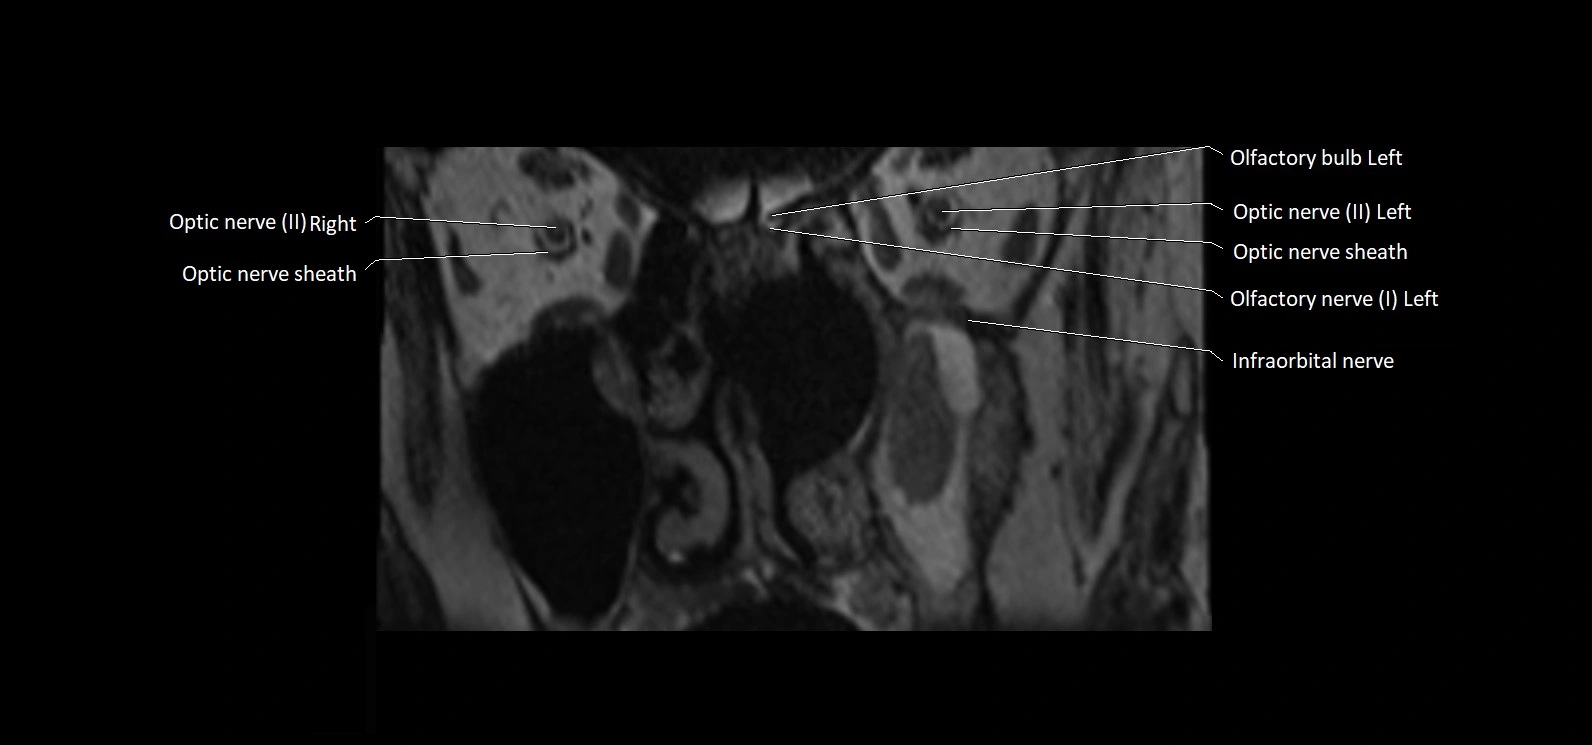

MRI images

image